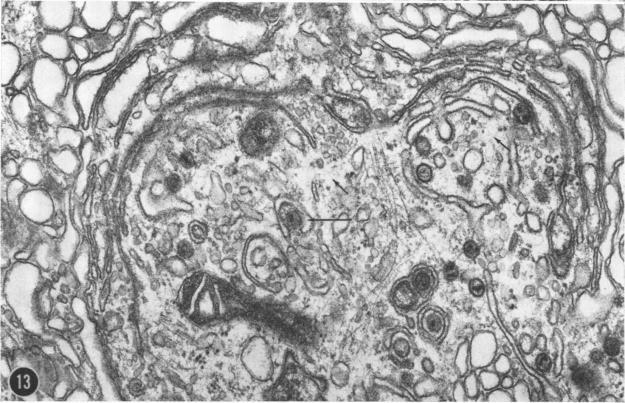

Ultrastructural observations on a new viral isolate, designated iguana virus, indicate that it is consistently present in intranuclear inclusions, possesses a +/- 115-nm nucleocapsid, ranges from 165 to 300 nm in diameter in the enveloped form, and exhibits cubic symmetry (probably 162 capsomeres). It is concluded that it is a herpes-type virus, the morphological evidence being in agreement with and supporting the biological and physical characteristics presented by Clark and Karzon. Several fine-structural features, among them the encapsidization of small 35-nm hexagonal bodies and the viral membrane envelope enclosure of cell-derived moieties are presented and discussed.

对一种新的病毒分离株(命名为鬣蜥病毒)的超微结构观察表明,它始终存在于核内包涵体中,具有约115纳米的核衣壳,包膜形式的直径范围为165至300纳米,并呈现立方对称(可能有162个壳粒)。得出的结论是,它是一种疱疹型病毒,形态学证据与克拉克和卡尔宗提出的生物学和物理特征一致并提供了支持。文中展示并讨论了几个精细结构特征,其中包括35纳米的小六角体的衣壳化以及细胞衍生部分的病毒膜包膜包裹。